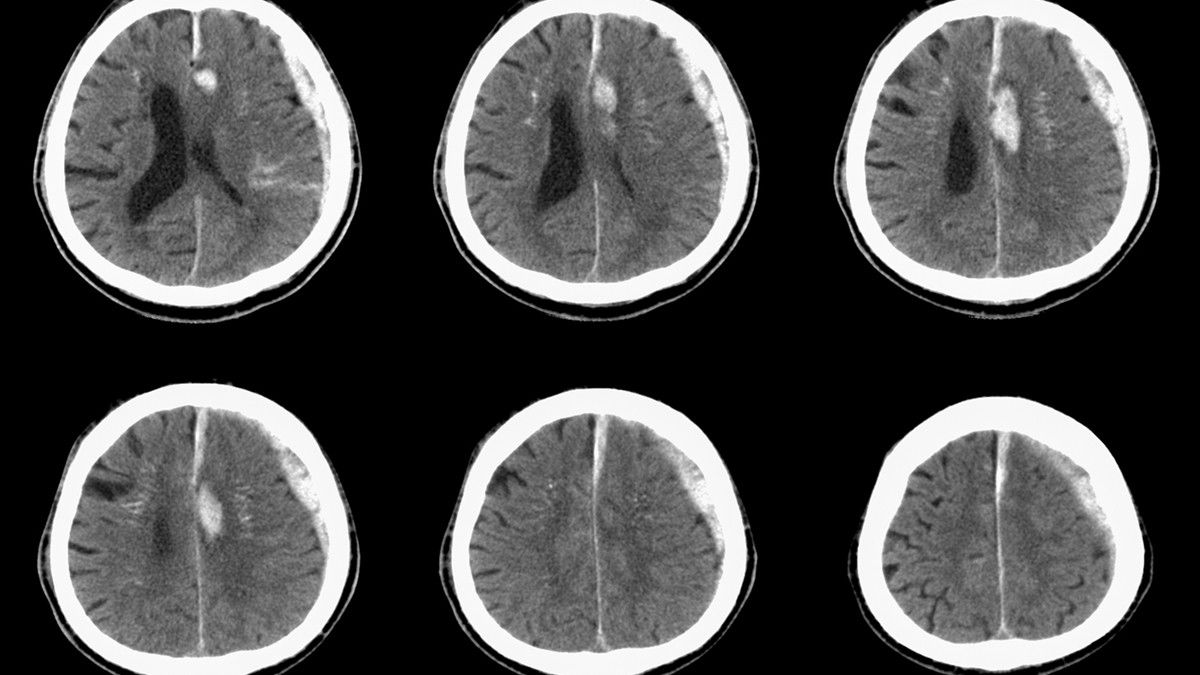

Hematoma subdural (SDH atau subdural hematoma) merupakan perdarahan di antara lapisan otak, yakni lapisan arachnoid dan lapisan dura (meningeal).

"Ada tiga tipe SDH berdasarkan waktunya, yaitu SDH akut, SDH subakut, dan SDH kronis. SDH akut terjadi kurang dari 72 jam, SDH subakut 3-7 hari setelah cedera, dan SDH kronis terjadi dalam beberapa minggu," ungkap dr. Sepriani Timurtini Limbong.

Lalu, tes pencitraan kepala beberapa kali sering diterapkan untuk mengamati apakah penyakit tersebut membaik atau tidak.

Sementara itu, penanganan hematoma subdural yang parah biasanya membutuhkan pembedahan. Tujuannya untuk mengurangi tekanan pada otak.

"Penanganannya tergantung derajat keparahan. Biasanya akan dilakukan pemeriksaan dulu, seperti MRI atau CT scan. Kemudian, ditentukan apakah harus dilakukan pembedahan atau ada pilihan lain," ungkap dr. Sepriani.